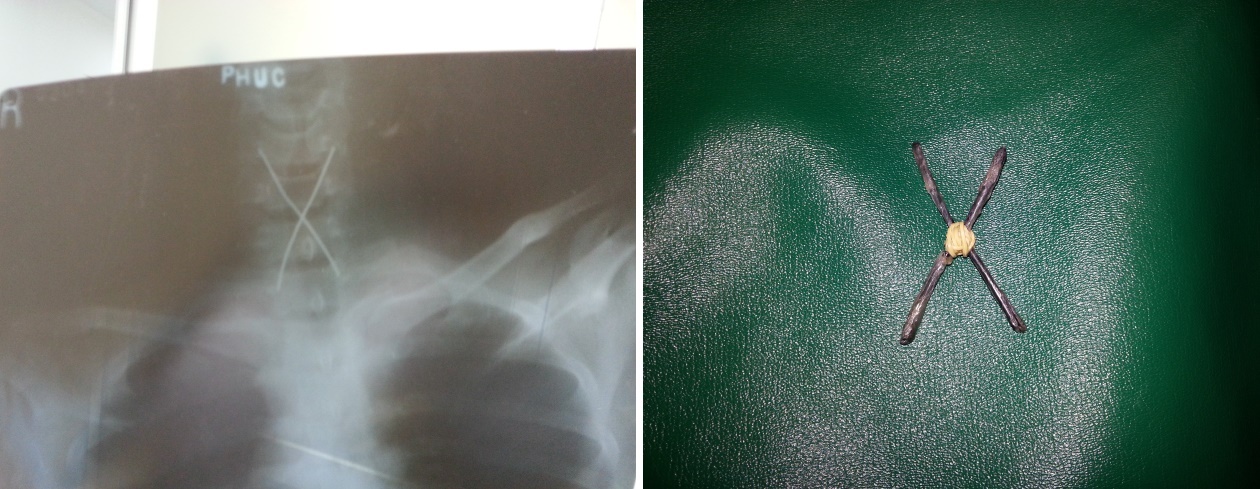

“Bệnh nhân đã chủ động nuốt 2 que sắt nhọn, giấu ở cuống họng để qua mặt lực lượng an ninh. Nhưng không may, que sắt đã đi sâu vào thực quản và mắc kẹt không thể lấy ra được. Khi được đưa tới bệnh viện cấp cứu, bệnh nhân trong tình trạng nguy kịch. Ê-kíp trực phải xử lý khẩn cấp để lấy dị vật ra nhằm tránh tổn thương thêm những bộ phận khác”, BS. Phong chia sẻ về một ca nội soi lấy dị vật đặc biệt đã thực hiện.

| Hai que sắt được buộc với nhau bằng dây chun để nuốt vào cuốn họng nhưng bị mắc kẹt với 4 đầu nhọn ghim thẳng vào thực quản.